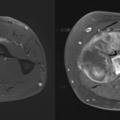

Concernant les tumeurs des membres, on distingue premièrement les lésions graisseuses, qui sont majoritairement représentées par les lipomes bénins. Ces lésions ne nécessitent pas d’examen complémentaire si elles ont une taille inférieure à 5 cm en situation profonde (intramusculaire) ou 10 cm en situation superficielle (dans la graisse sous-cutanée au-dessus des fascias musculaires). Au-dessus de cette limite de taille, il est recommandé de réaliser une imagerie par résonance magnétique (IRM), à la recherche de signes d’atypie. L’objectif est de reconnaître les potentiels liposarcomes et les tumeurs graisseuses atypiques (liposarcomes bien différenciés). Dans les autres cas de figure, c’est-à-dire pour les tumeurs non graisseuses, ou les pseudotumeurs, ou pour les tumeurs osseuses qui ne sont pas aisément caractérisables, le recours à l’IRM doit être systématique (figure). Certaines lésions restent d’orientation difficile, et il est de rigueur de prôner la prudence en envoyant le patient dans un centre expert et/ou en organisant une surveillance radioclinique. Pour inciter à la prudence, on évoque volontiers les cas souvent décrits des lésions sarcomateuses prises par erreur pour des hématomes et les radiographies normales des sarcomes osseux de l’enfant au stade précoce. Une évolution clinique péjorative doit être systématiquement accompagnée d’une investigation radiologique par IRM.